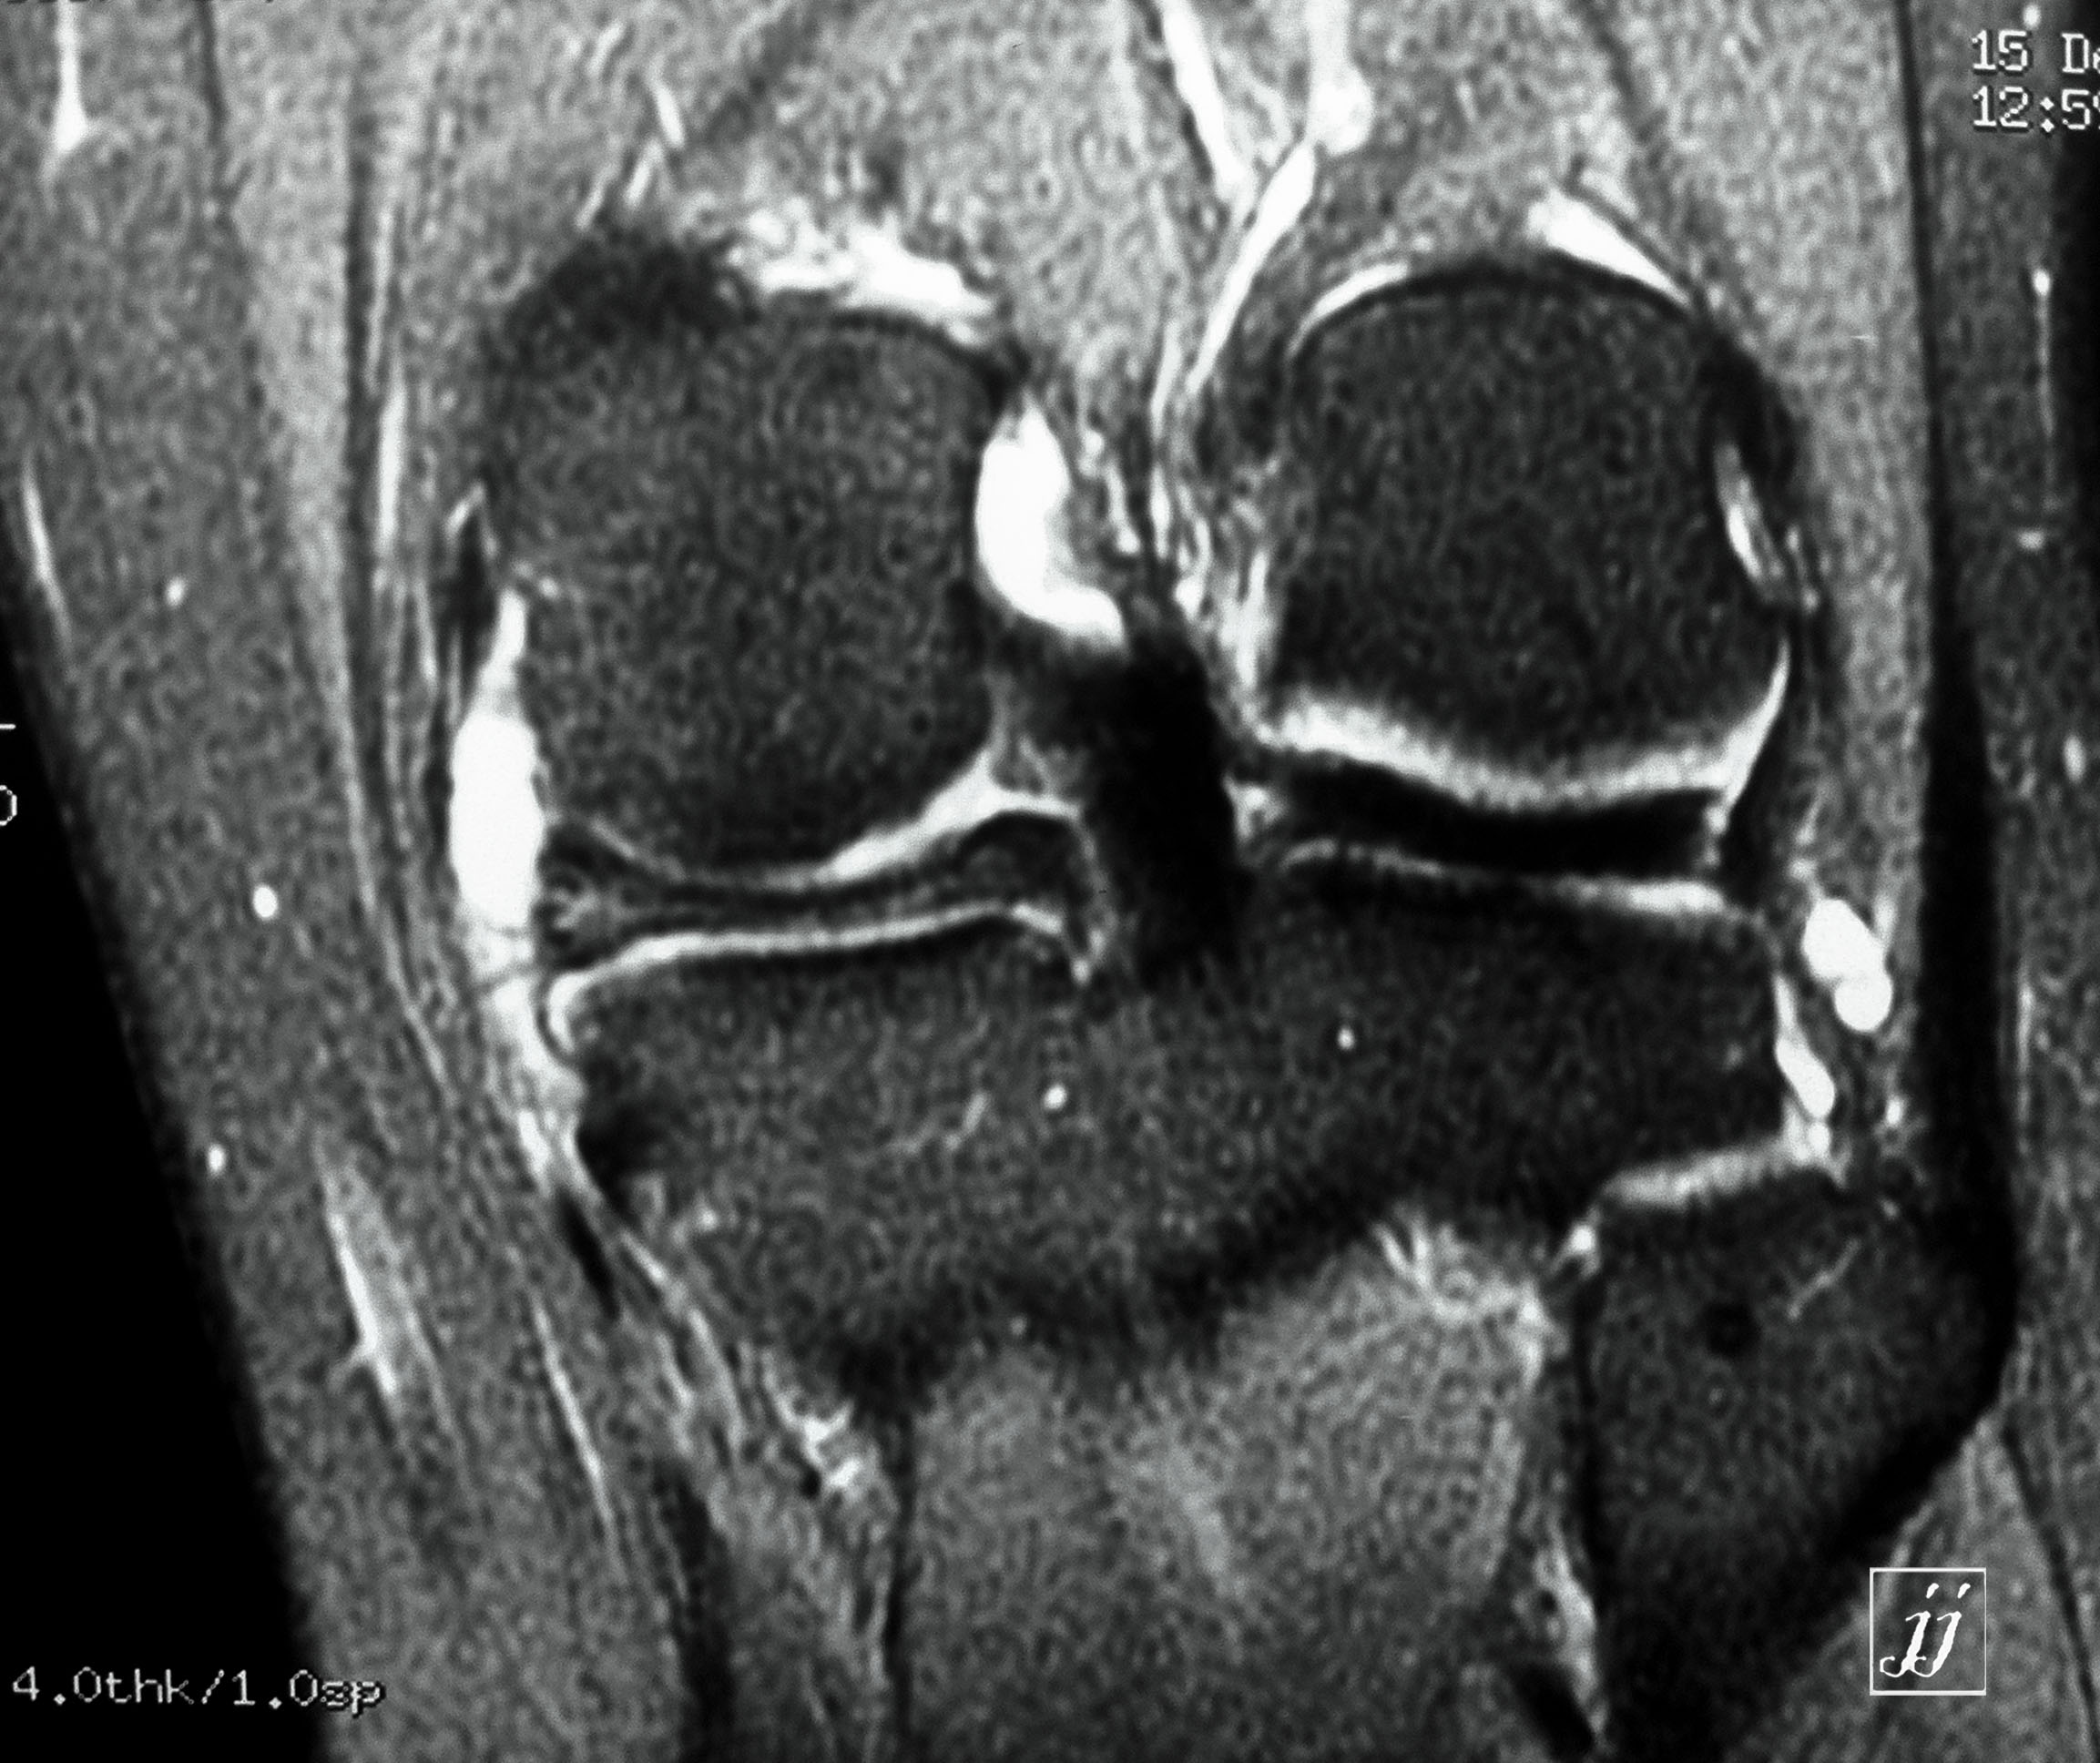

MSK- bi lateral popliteal cyst (9)